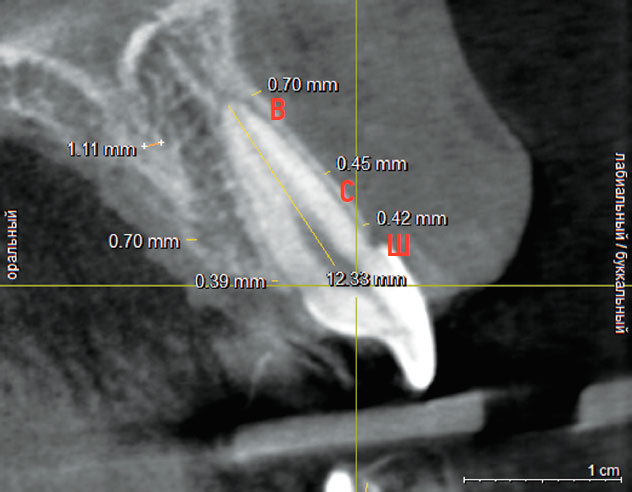

Рис. 2. Измерение плотности компактной пластинки с вестибулярной стороны в области зуба 1.1

Fig. 2. Compact plate density measurement in the vestibular part of tooth 1.1